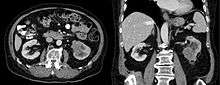

Collecting duct carcinoma

Collecting duct carcinoma (CDC) (also known as Bellini duct carcinoma[1]), is a type of kidney cancer that originates in the papillary duct of the kidney. It is rare, accounting for 1-3% of all kidney cancers.[2] It is also recently described; a 2002 review found just 40 case reports worldwide.[3] Previously, due to its location, CDC was commonly diagnosed as renal cell carcinoma or a subtype of renal cell carcinoma.[4] However, CDC does not respond well to chemotherapy drugs used for renal cell carcinoma, and progresses and spreads more quickly.